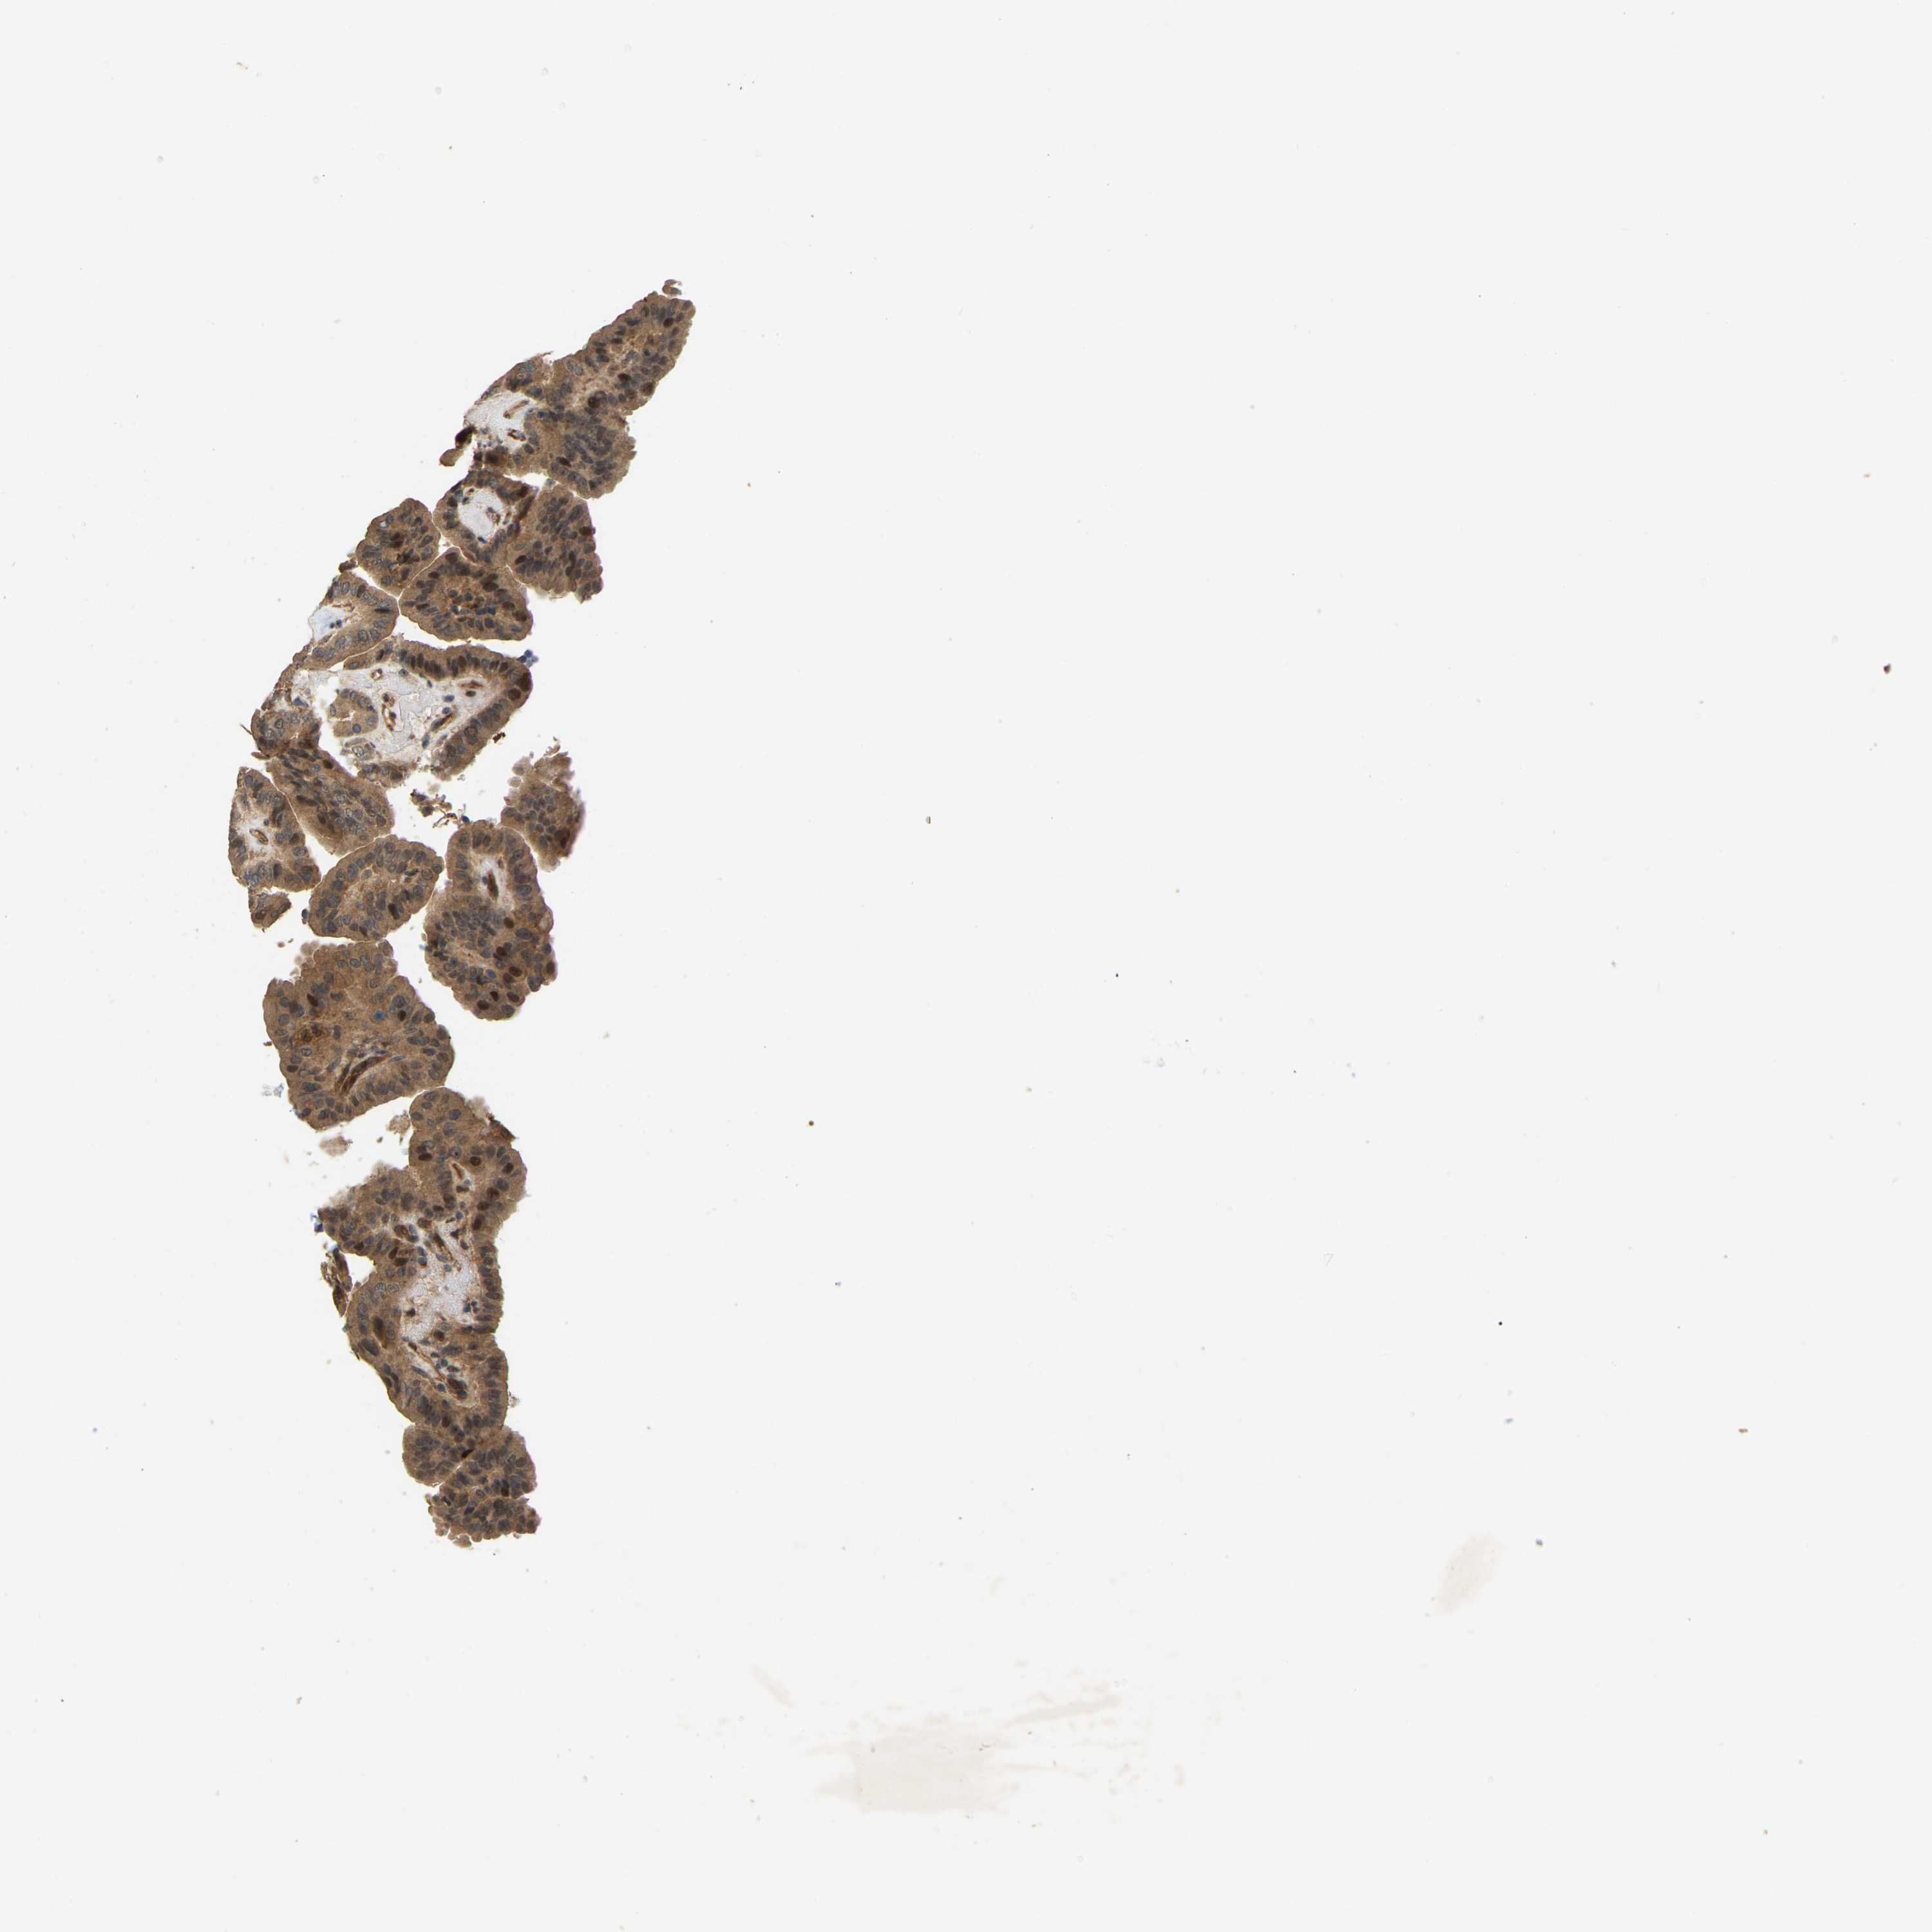

THYROID CANCER - Protein expressioni

A mouse-over function shows sample information and annotation data. Click on an image to view it in a full screen mode. Samples can be filtered based on level of antibody staining by selecting one or several of the following categories: high, medium, low and not detected. The assay and annotation is described here.

Note that samples used for immunohistochemistry by the Human Protein Atlas do not correspond to samples in the TCGA dataset.

Antibody stainingi

Antibody staining in the annotated cell types in the current human tissue is reported as not detected, low, medium, or high, based on conventional immunohistochemistry profiling in selected tissues. This score is based on the combination of the staining intensity and fraction of stained cells.

Each image is clickable and will lead to virtual microscopy that enables deeper exploration of all samples and also displays staining intensity scores, fraction scores and subcellular localization as well as patient and tissue information for each sample.

Antibody HPA008183

Antibody HPA053882

Antibody CAB019313

Staining

High

Medium

Low

Not detected

Intensity

Strong

Moderate

Weak

Negative

Quantity

>75%

75%-25%

<25%

None

Location

Nuclear

Cytoplasmic/membranous

Cytoplasmic/membranous,nuclear

Papillary adenocarcinoma, NOS

Follicular adenoma carcinoma, NOS